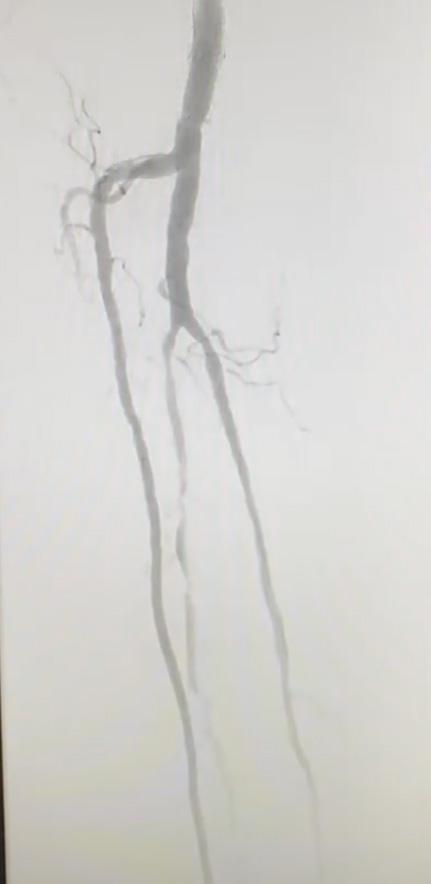

Tackling difficult acute limb ischemia cases with an endovascular-first approach using Lightning Bolt 7 computer assisted vacuum thrombectomy

Adam Reichard, MD, discusses the use of Lightning Bolt 7® computerassisted vacuum thrombectomy (CAVT TM) as a first-line option across a wide spectrum of challenging lower extremity acute limb ischemia (ALI) cases, including patients with Rutherford classification IIb ALI.

Two cases stick out for Reichard where he used Lightning Bolt 7 (Penumbra) computer-assisted vacuum thrombectomy (CAVT) as his firstline therapy for patients who require urgent management for lower extremity ALI.

Both patients were diagnosed with Rutherford IIb lower extremity acute limb ischemia. And both saw clinical improvement following use of the Lightning Bolt 7 device, notes the vascular surgeon in the TriHealth hospital system based in Cincinnati, Ohio.

The level of threat to the limb is so great, open surgery would be the traditional approach. Yet, as Reichard has observed in recent years, the landscape has shifted. In these patients, an endovascular-first approach is increasingly the go-to option. For evidence, he points to the STRIDE study, which looked at 30-day outcomes after firstline use of the Indigo and Lightning portfolios in cases of ALI, including Rutherford I, IIa and IIb patients.

“If you’re talking to vascular surgeons who treat this disease pathology, they would agree that it is routine to start with an endovascular approach in someone who has Rutherford I or IIa ischemia, but, when you get into IIb territory, and you know it’s a more threatened limb, then people might be a little more reluctant,” Reichard explains. “However, the STRIDE study did a great job showing that, even in patients with Rutherford IIb ALI, at 30 days you’re going to salvage more limbs and mortality is going to be lower if you start with percutaneous thrombectomy, including computer-assisted vacuum thrombectomy technology, as opposed to open surgery.”

Thirty-day outcomes from STRIDE—a prospective, single-arm observational study carried out at 16 international sites among 119 patients with lower extremity ALI— showed rates of 98.2% for limb salvage, 89.4% for patency, 3.4% for mortality and 4.2% for periprocedural major bleeding.1 This compares to rates of 83.1% (limb salvage),2 78.6% (patency),3 13.2% (mortality),4 and 21% (major bleeding)5 in the setting of